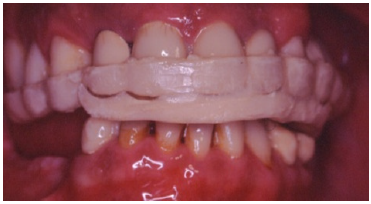

The Caucasian 53-year-old male patient was seeking treatment. His chief complaint was difficulty in chewing and his anticipation for a fixed restoration (Figure 1).

Figure 1: Preoperative intraoral frontal view.

Figure 19: Occlusal splint for the protection of final restoration.

Figure 20: Final restorations after cementation of the all ceramic veneers.